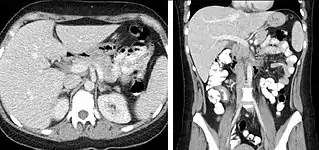

The most common technique is to perform portal venous phase imaging in the abdomen and pelvis (approximately 60-90 seconds after contrast administration, figure 2). This results in near optimal contrast opacification of the majority of the solid abdominal organs and it is used for a wide variety of indications: nonspecific abdominal pain; hernia; infection; masses (with a few exceptions such as hypervascular, renal, and some hepatic tumors); and in most follow-up examinations. As a general rule, this single phase is adequate unless there is a specific clinical indication that has been shown to benefit from other phases.

FIGURE 2. Contrast enhanced CT demonstrating parenchymal enhancement of the intra-abdominal organs in the portal venous phase (axial left, coronal reformat right).